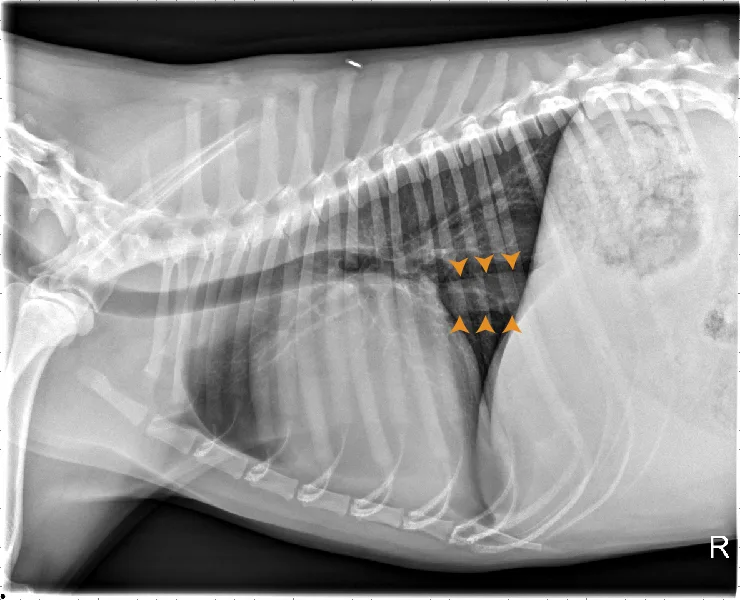

FIGURE 8 DV (left) and left lateral (right) projections consistent with left-sided CHF in a dog with advanced MMVD. Pulmonary venous distention (arrowheads), an interstitial to alveolar pattern in the perihilar region extending caudodorsally, cardiomegaly, and aerophagia are present. VHS, VLAS, M-VLAS, and VRHi collected from the left lateral view are 10.9, 2.8, 4.8, and 3.2, respectively.